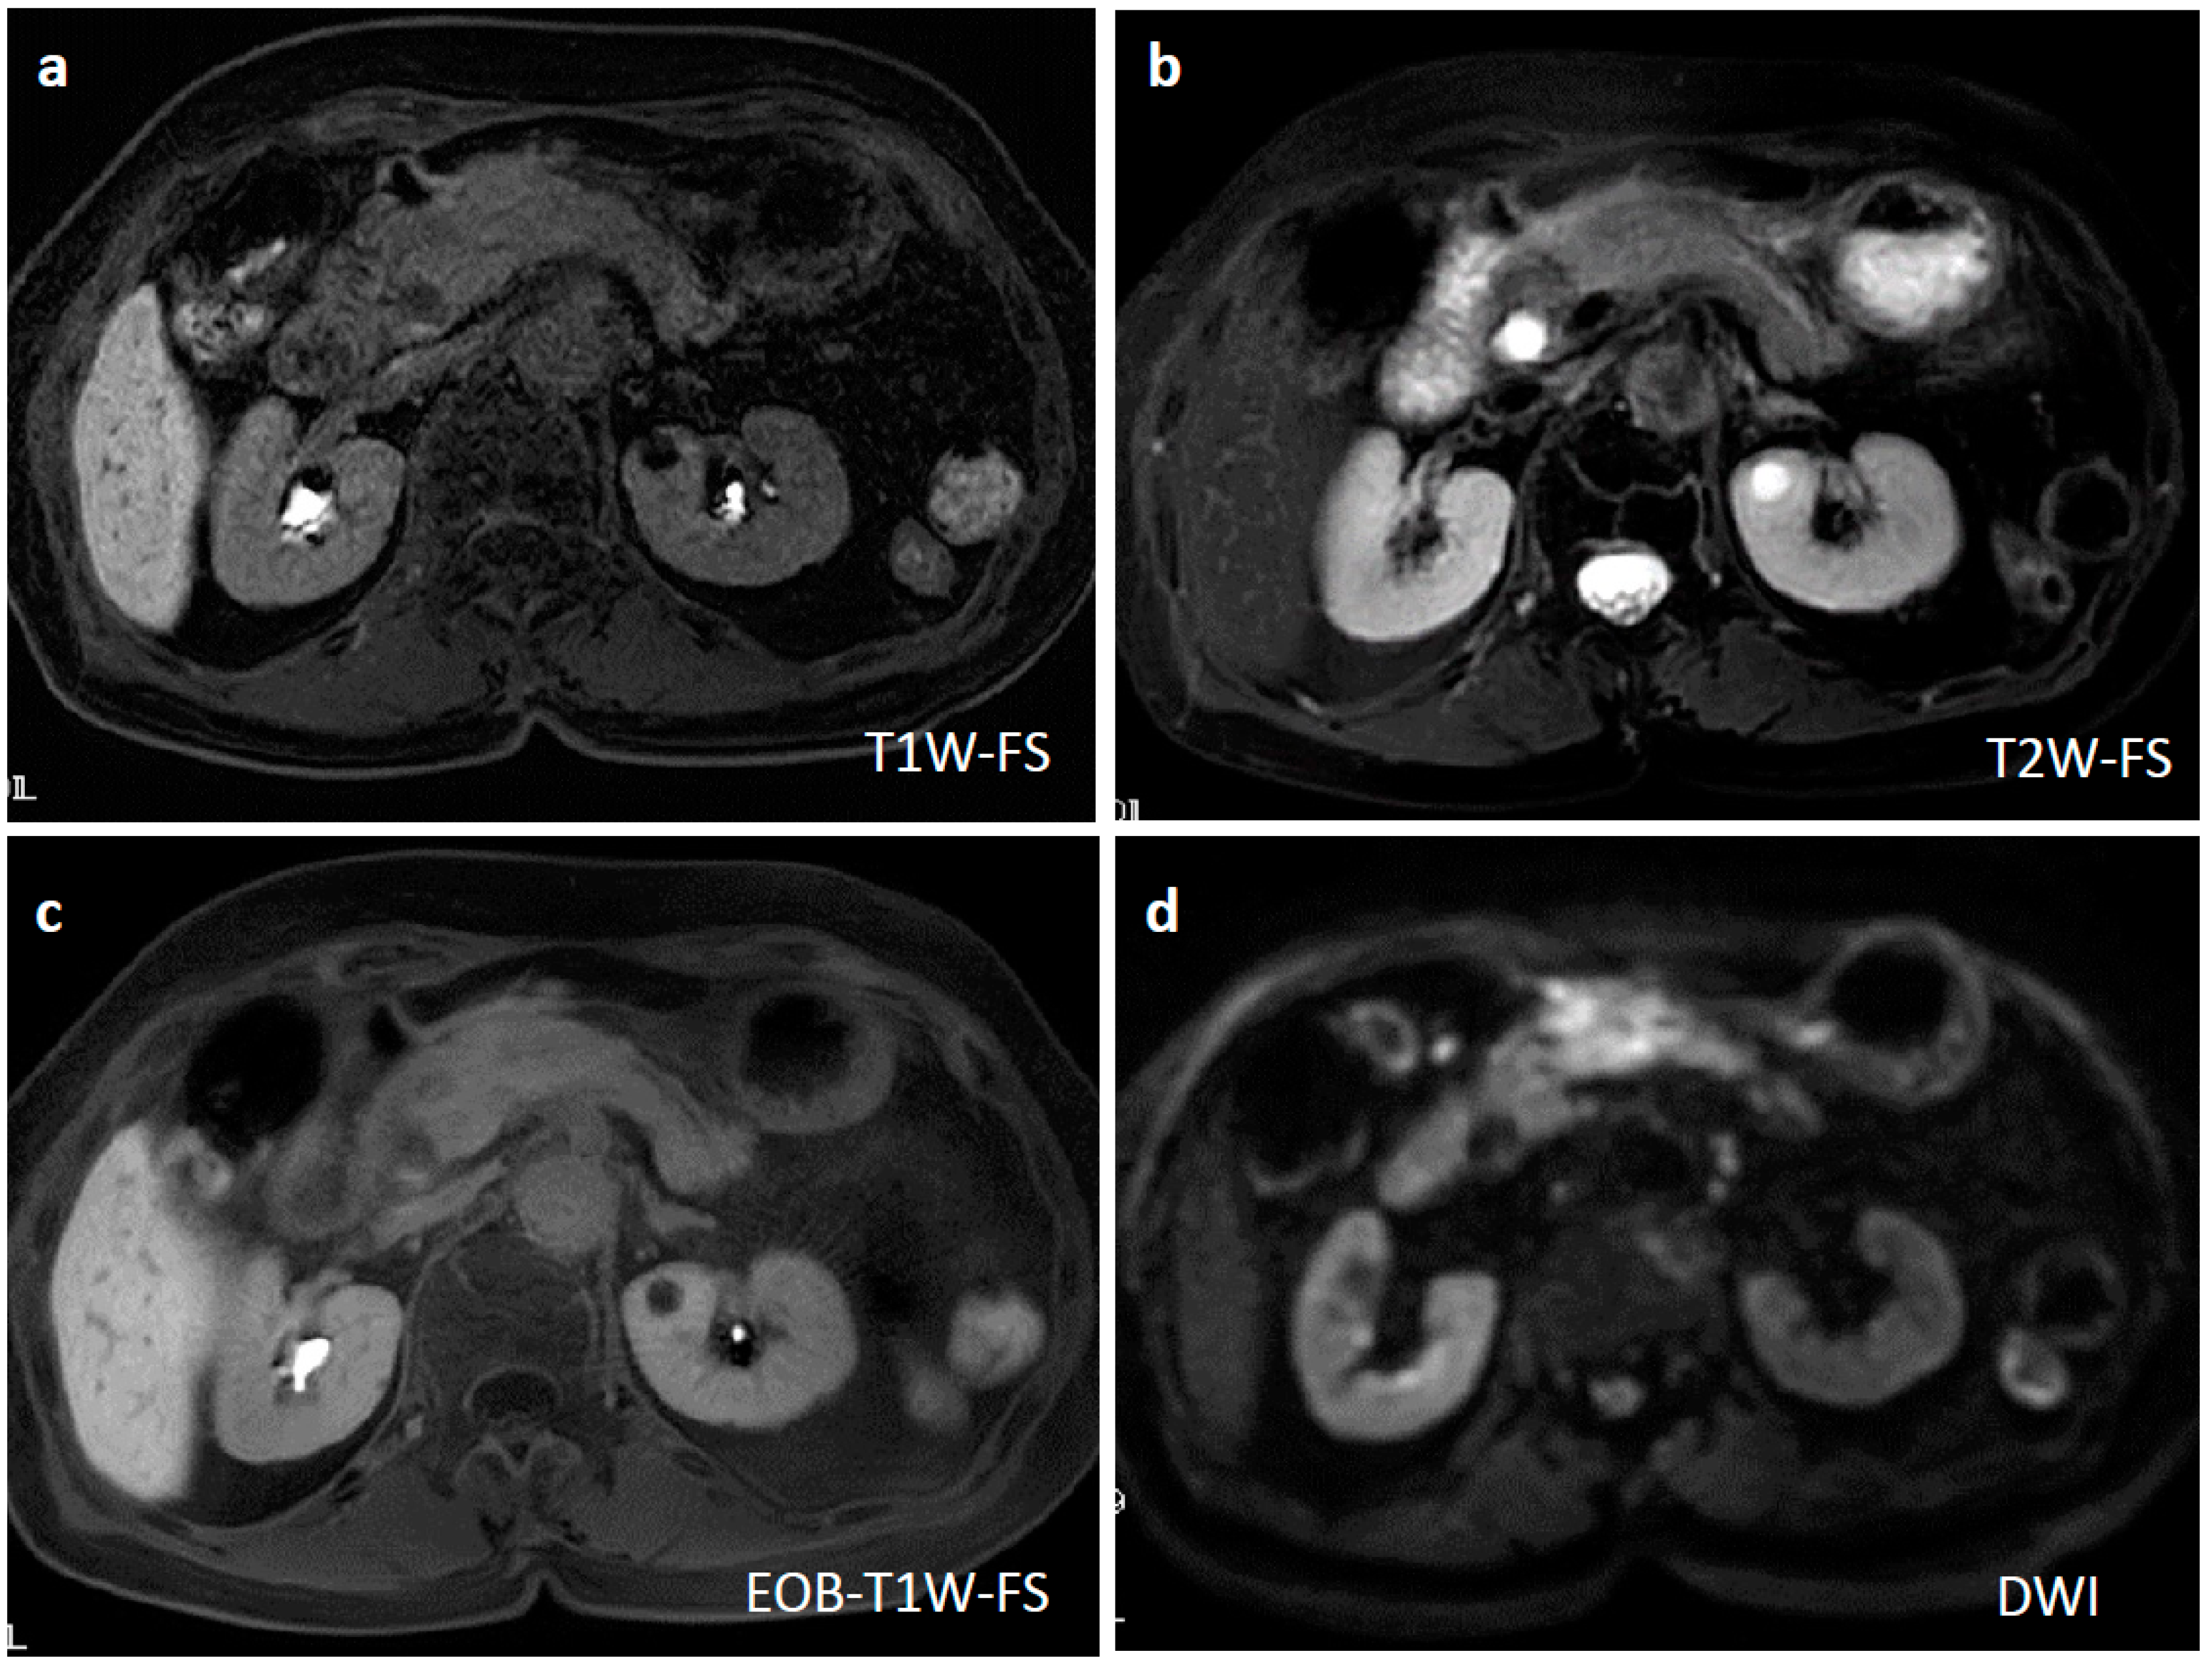

2. Case Presentation